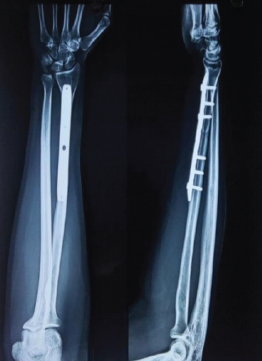

Successful Management of Atypical Bilateral Galeazzi Fractures with Unique Dorsal Displacement: A Case Report

Warid Altaf , Amit Chaudhari , Parag Sancheti